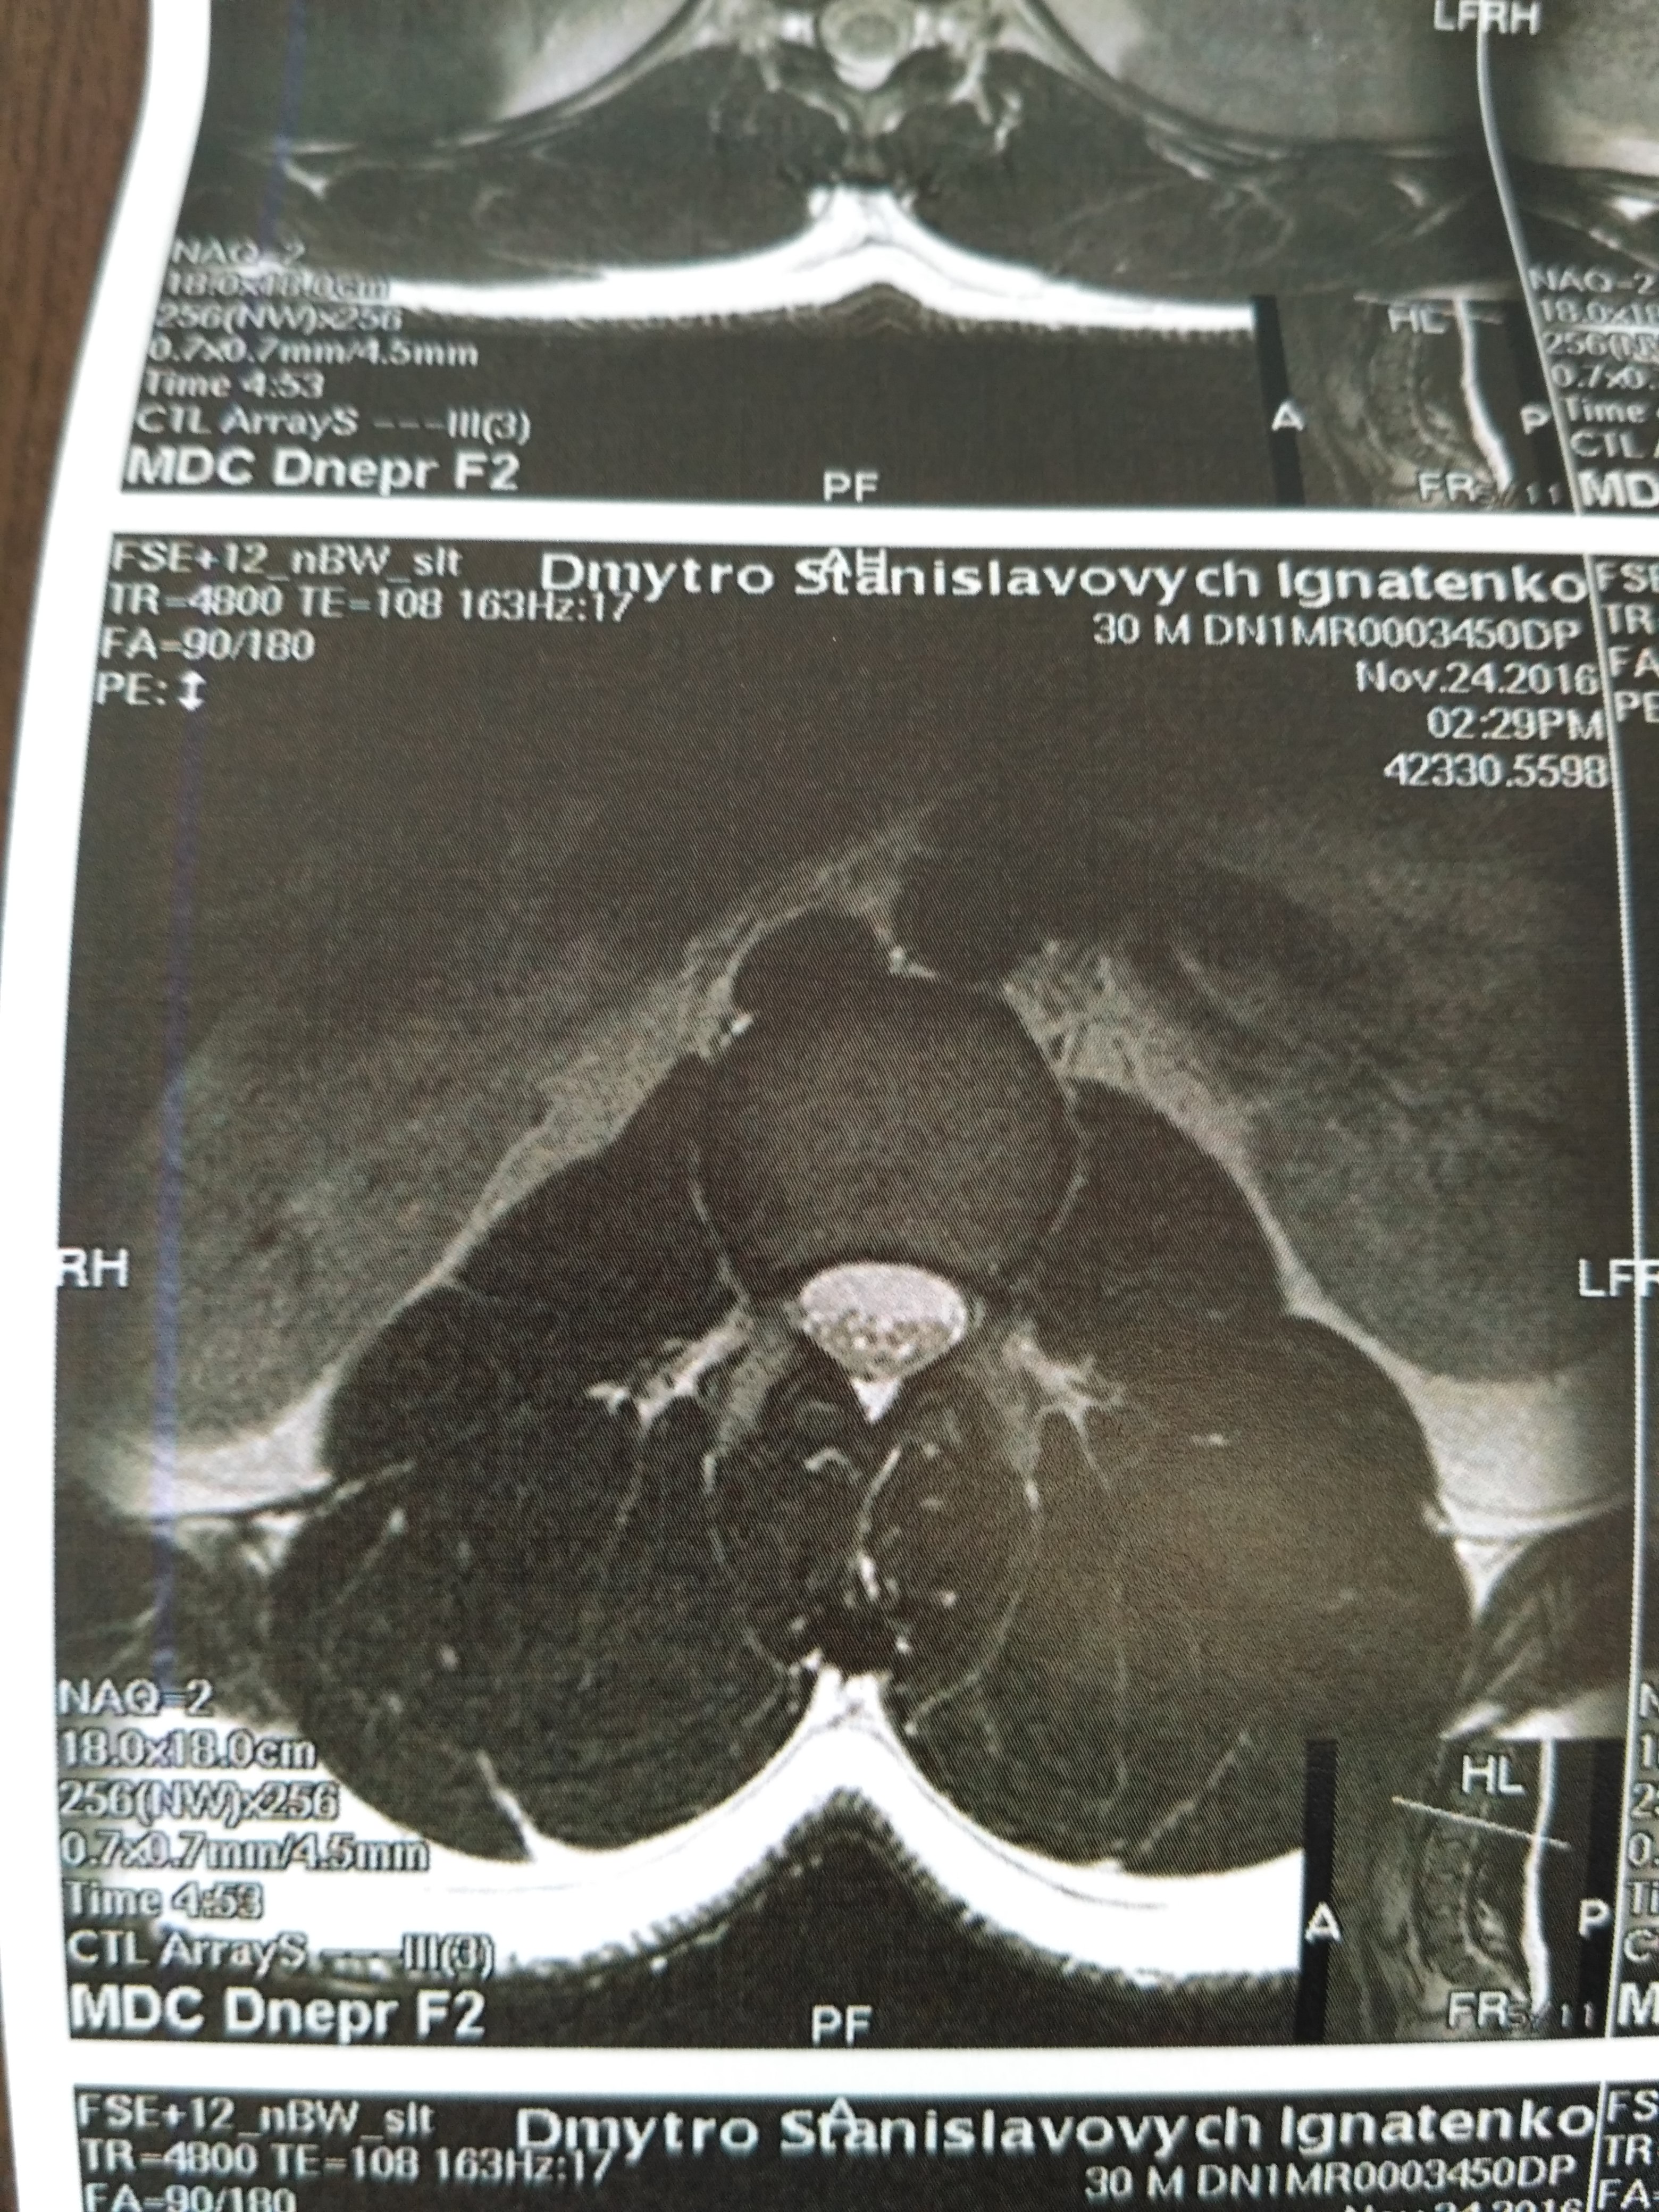

Тренировки с межпозвоночной грыжей.